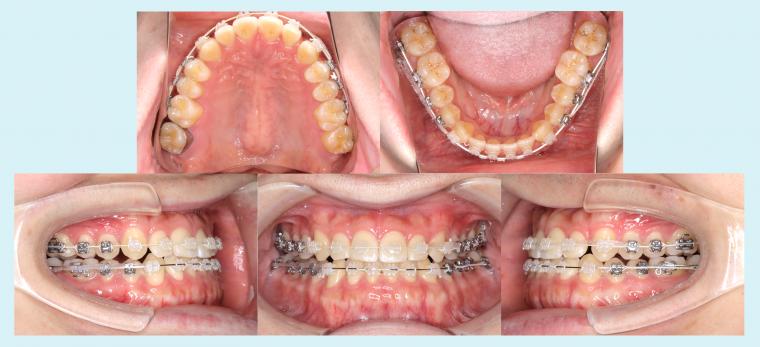

#46 下顎歯列の後方移動を行った症例